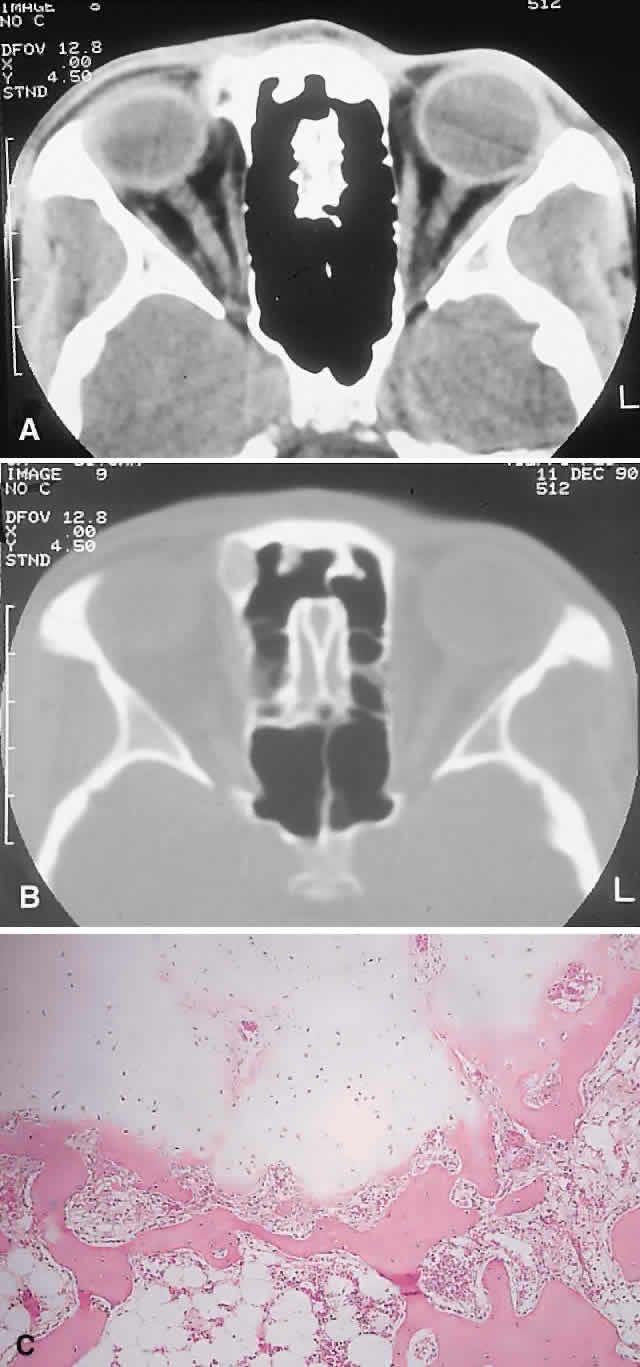

PRESENTATION. A superolateral mass effect encompassing weeks to years is the typical mode of presentation. This leads to inferior globe displacement, proptosis, and diplopia in upgaze (Fig. 5). There may be associated headache or pain; one third of patients recall a prior trauma.70,71

Fig. 5. A 41-year-old man had a 2-year history of left proptosis and headaches. A. Examination found 6 mm of proptosis with 4 mm of inferior ocular displacement. B. CT showed an osteolytic mass arising from the superolateral frontal bone and extending into the orbit. C. Histologically, a classic picture of cholesterol granuloma was apparent, with numerous cholesterol clefts surrounded by granulomatous inflammation containing foreign body giant cells (hematoxylineosin, × 20).

IMAGING. The granuloma arises in the diploë of the frontal bone, causing expansion and eventually erosion of the inner and outer tables. CT reveals it to be osteolytic, with a density equivalent to brain, and occasional intralesional bone fragments.72 Mature lesions display high T1 and T2 signal intensities on MRI.73,74 The most commonly evoked differentials in this setting are dermoid cysts and lacrimal gland carcinomas.

HISTOPATHOLOGY. These cysts usually contain yellow-brown viscous material with friable tissue and porous bone at the periphery. Histologically, the principal feature is the dominance of cholesterol clefts surrounded by granulomatous inflammation with conspicuous foreign body giant cells. A variable fibrous stroma is present and usually contains extensive blood-derived debris in the form of extracellular and intracellular hemosiderin as well as more recent hemorrhage.70,75